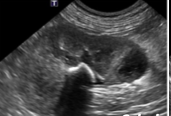

Q

DX? (reins)